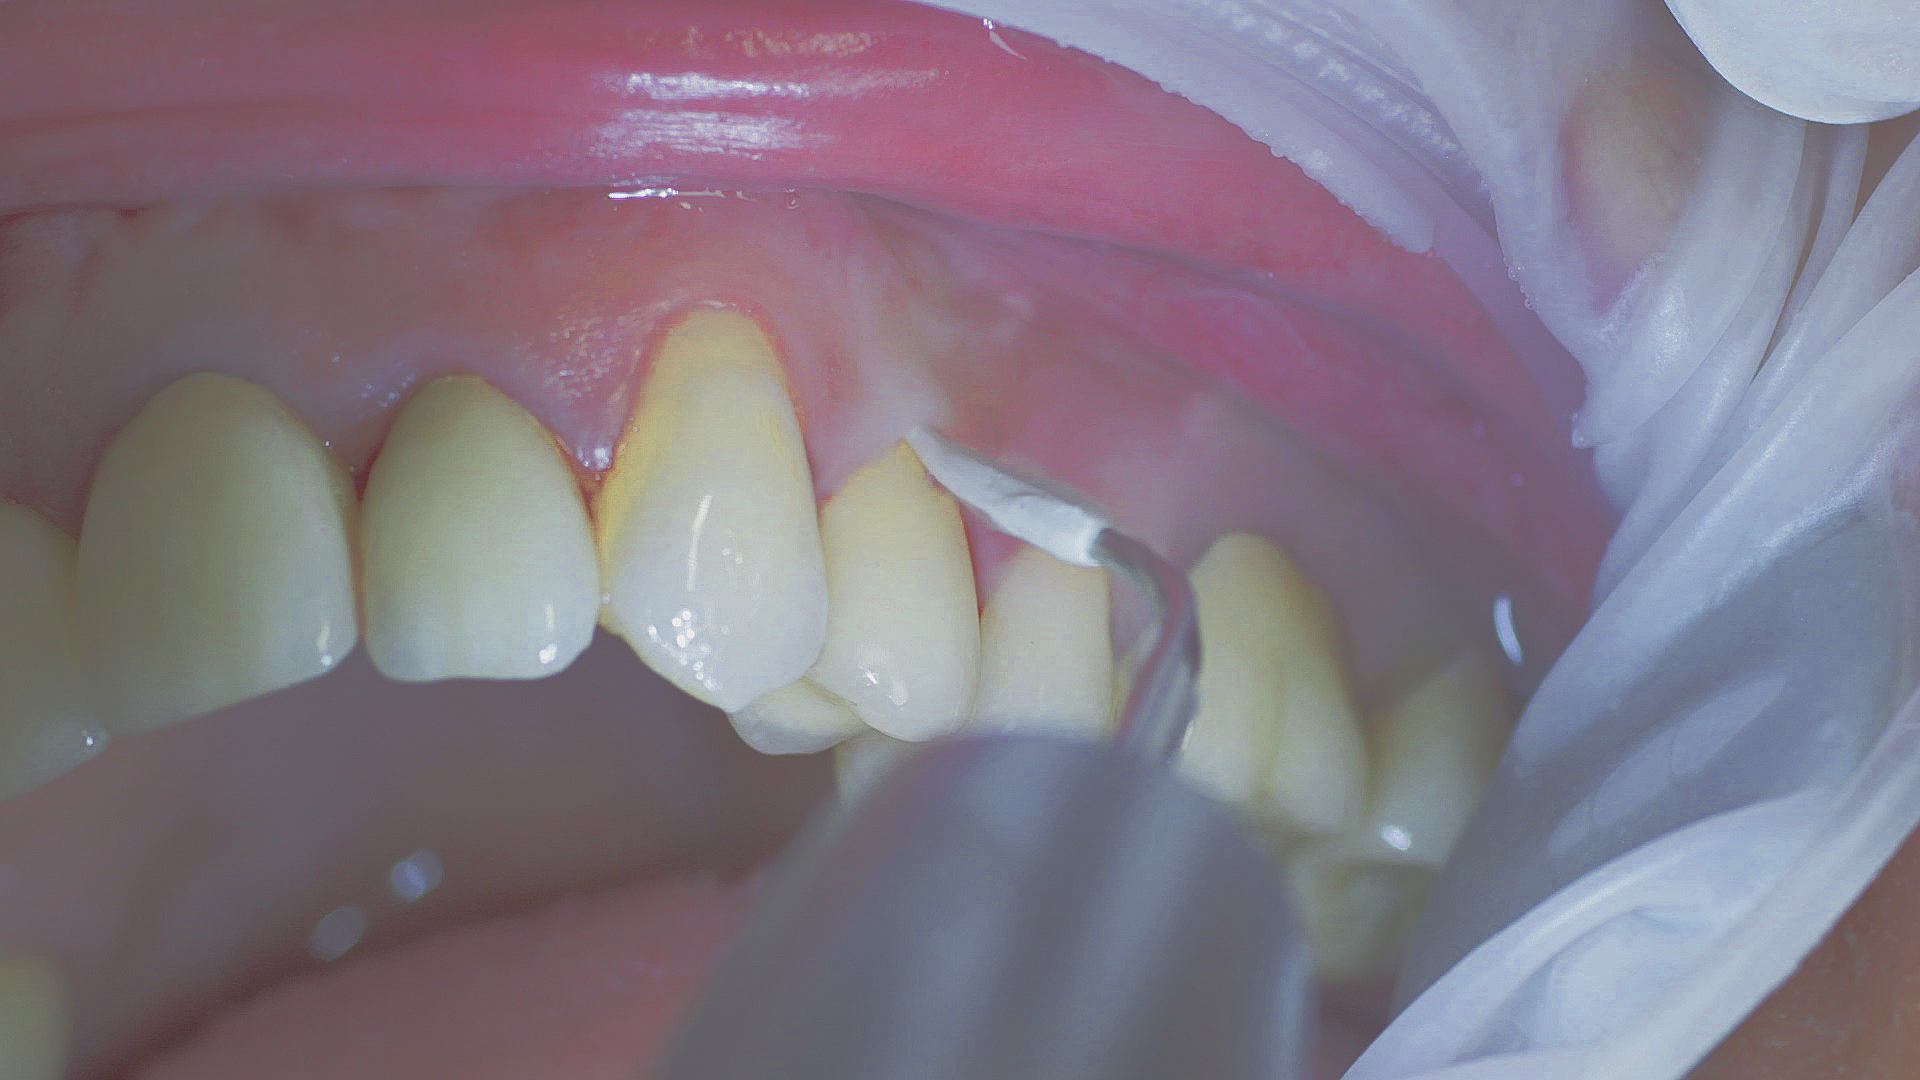

In the periodontal aftercare subsequent to implantation, soft (biofilm) and hard coatings are regularly professionally and mechanically removed.[16, 17] In the subgingival and supragingival areas, ultrasonic devices are generally used for this (Fig. 4), in combination with manual instruments where necessary. Alternatively, subgingival air polishing can be used in combination with periodontal attachments and powders.[18]

Ultrasound devices are particularly suitable for UPT

Fig. 4: Ultrasound devices are particularly suitable for UPT, for example in combination with periodontal tips (W&H Tigon+ with 1P tip)